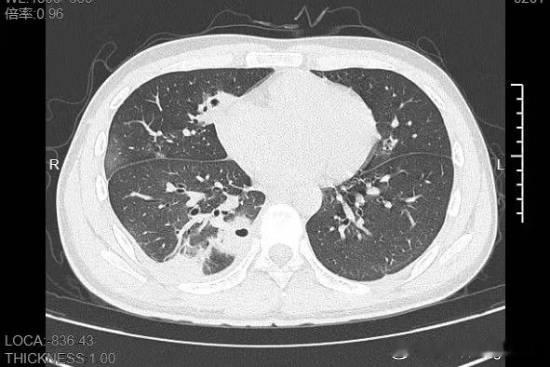

20岁男生挤了颗脸上的痘痘 肺就出现10多个洞近日,浙江宁波,20岁的小林是名大二学生,前段时间为了准备考试,熬了几晚后脸上冒出一颗黄豆大小的痘痘。“又红又肿的很难看,我就想着挤掉能快点好。”他回忆道,当时没洗手就对着镜子挤痘痘,脓水挤出来时,他还觉得终于清爽了。可过了几天,痘痘依旧化脓了,更糟糕的是,小林开始发烧咳嗽咳痰,即便吃了退烧药也只是暂时退下去,右下胸部传来的疼痛像有根针在扎,深呼吸、咳嗽时更是疼得他直冒冷汗。熬到第三天,小林已经烧到39℃,赶紧来到宁波大学附属第一医院就诊。接诊的丁群力主任医师一看他的症状,立刻安排了CT检查。结果显示:小林的肺里有十几个空洞,部分肺组织已经坏死,这是典型的血源性肺脓肿。进一步的细菌培养和基因检测揭开了真相,小林的血液里检出了金黄色葡萄球菌,这种细菌,就藏在每个人的皮肤表面。“‘罪魁祸首’就是那颗被挤掉的痘痘。”丁群力解释,“这颗痘痘长在脸部‘危险三角区’,挤痘痘时的压力把细菌推进了血管,引发了败血症,接着细菌顺着血流跑到肺部,侵蚀肺组织。”万幸小林年轻,身体素质底子好,对药物也较为敏感,经过12天的抗生素治疗,最终顺利康复出院。